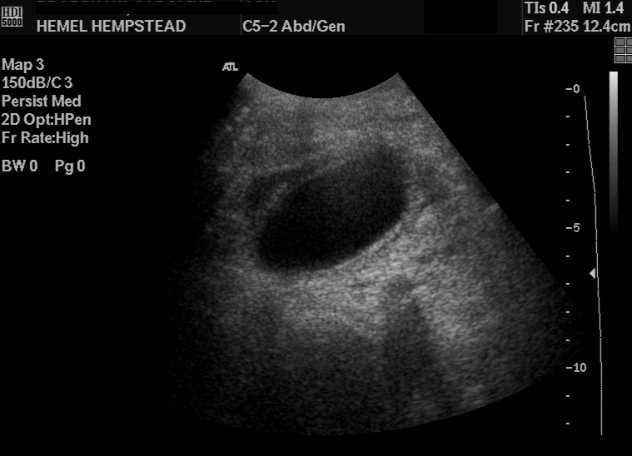

I had an abdominal ultrasound done and kaiser said i have a thickening of the gallbladder wall in multiple areas, kidney cysts and a hepatic hemangioma. Thickening of the gallbladder wall is a relatively frequent finding at diagnostic imaging studies. Diffuse gallbladder wall thickening more than 3 mm by ultrasound, can be seen in such primary gallbladder.

Thickening of the gallbladder wall is always abnormal, although the significance of the thickening is highly dependent upon the underlying disease process. I have had 2 radiologists'contradicting reports.one noted a minimal gallbladder wall thickening.the other radiologist found the parietal walls normal.my blood tests are normal.fatty food does not trigger any pain.first. The liver performs many functions, one of them is the utilization of worn out blood cells. I have not met any studies dedicated the subject of differentiating the former and the latter without laparoscopy or laparotomy yet, so do i not know myself how to solve this problem.